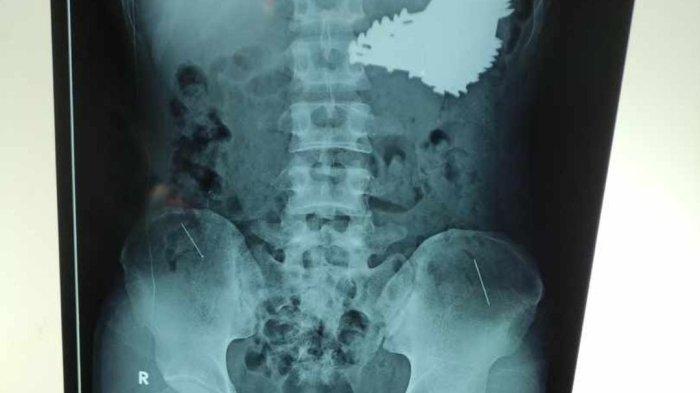

Paku yang berhasil diangkat tim bedah RSUD Indramayu dari lambung seorang pria.

Kejadian ini awalnya terungkap dari hasil pemeriksaan rontgen.

Foto rontgen itu memperlihatkan ada banyak paku berukuran besar yang bersarang di dalam lambung.

Sebanyak 70 batang paku yang bersarang di lambung pasien pun sudah berhasil diangkat.

“Total ada sebanyak 70 batang paku,” ujar dia.